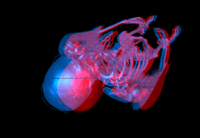

- supports stereo rendering

An anaglyph image of a human body rendered with ImageVis3D. |